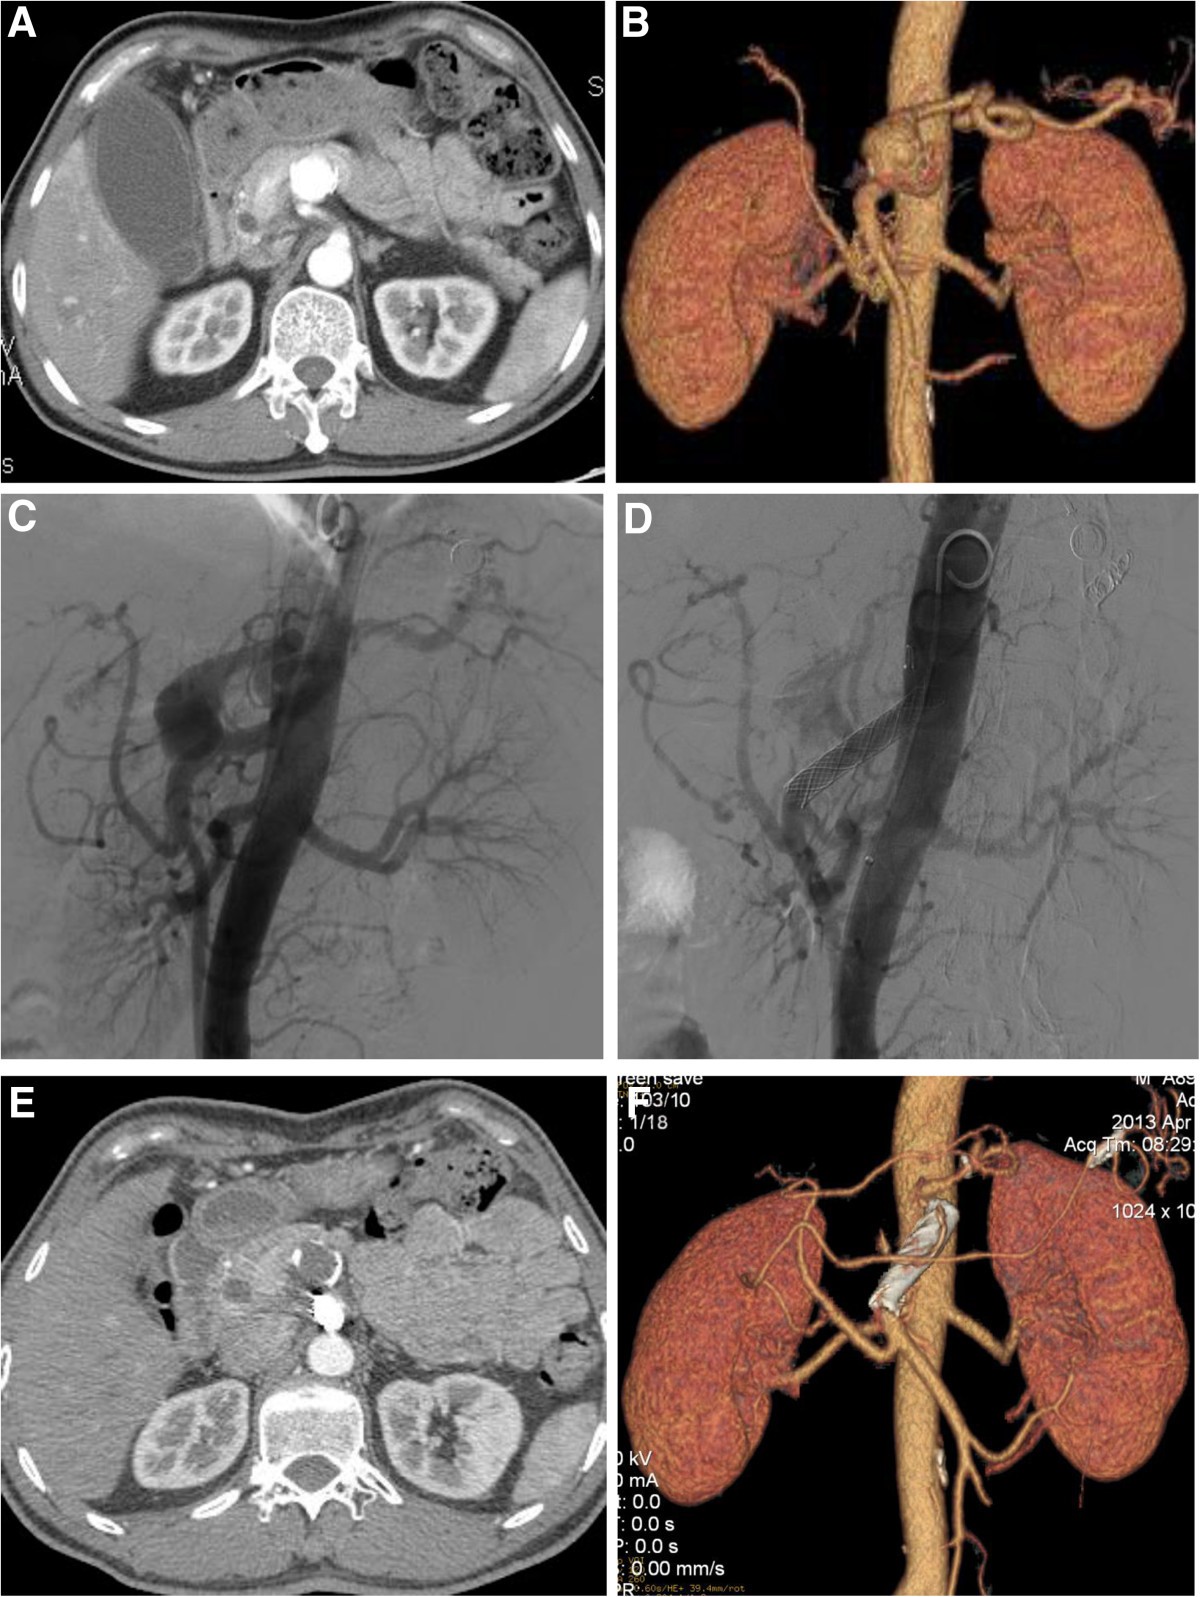

Main splenic artery embolization for atherosclerotic aneurysm. (A Coil Embolization For Splenic Artery Aneurysm Treatment options are dictated by. Although splenic artery aneurysms (saas) are the most common visceral aneurysm, there is a paucity of literature on the behavior of these entities. Of these 40 patients, aneurysms were located in the distal third of the splenic artery in 27 (67.5%), in the middle third in 9. There are multiple technical considerations for endoluminal exclusion. Coil Embolization For Splenic Artery Aneurysm.